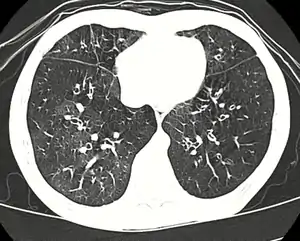

Medical imaging

Early in the disease chest radiography is typically normal but may show hyperinflation.[6] As the disease progresses a reticular pattern with thickening of airway walls may be present.[4][6] HRCT can also show air trapping when the person being scanned breathes out completely; it can also show thickening in the airway and haziness in the lungs.[11] A common finding on HRCT is patchy areas of decreased lung density, signifying reduced vascular caliber and air trapping.[6] This pattern is often described as a "mosaic pattern", and may indicate bronchiolitis obliterans.[6]